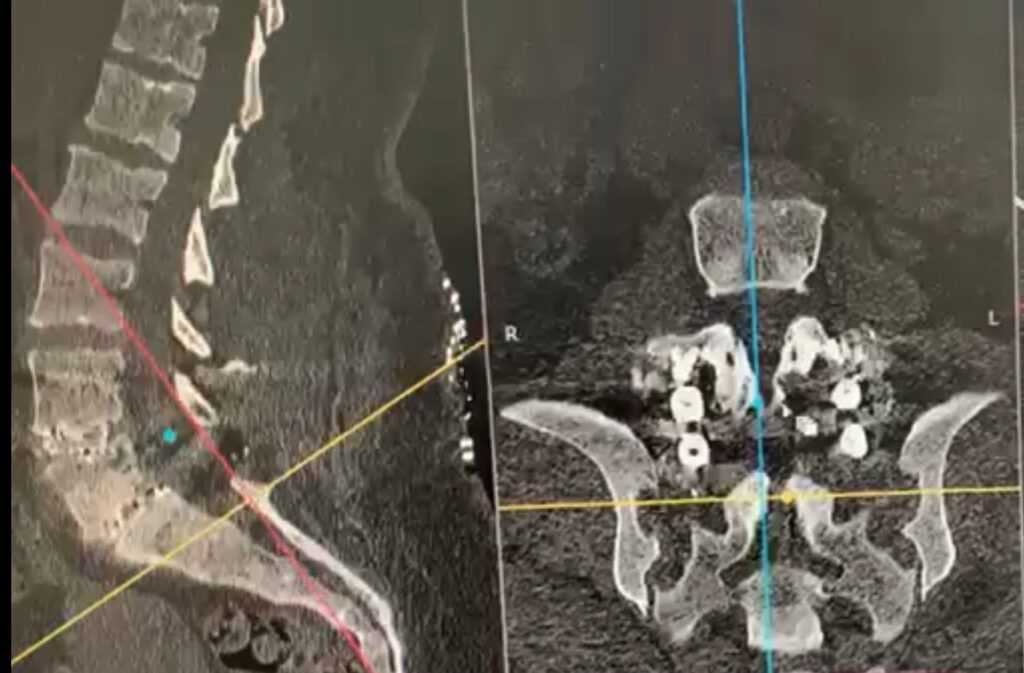

Cirugía de columna de paciente con espondilolistesis L4-L5, L5-S1 con instrumentación transpedicular.

Cirugía exitosa

Paciente de alta en 48 horas.